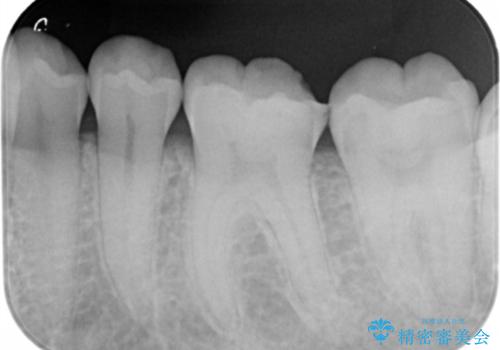

- 過去に他院で治療した詰め物が欠けてしみるとの事で来院。

プラスチックの樹脂での治療(保険)でされており虫歯が再発していました。

セラミックの詰め物は範囲が多ければ多いいほど割れてしまうリスクが高いため

今回はなるべく歯質を残したいとの事なのでゴールドの詰め物でご案内させて頂きました。ゴールドは範囲が多くても割れる心配がありません。また、虫歯の再発リスクが低いです。